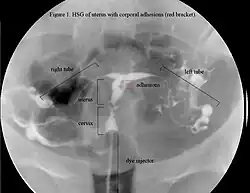

La historia del acontecimiento del embarazo seguido por la dilatación y el legrado liderizado por la amenorrea secundaria o a la hipomenorrea es común. La histeroscopia es el estándar de oro para el diagnóstico. 3 La proyección de sonohisterografía o histerosalpingografía podría revelar el grado de la formación de la cicatriz. El ultrasonido no es un método confiable de diagnosticar el Síndrome de Asherman. Los estudios de la hormona muestran los niveles normales constantes con la función reproductiva.

Mientras que IUA vuelven a formarse con frecuencia después de cirugía, las técnicas se han mejorado para prevenir la repetición de adherencias. Los métodos para prevenir la formación de adherencias incluyen en el uso de las barreras mecánicas (catéter de Foley, tubo (stent) especial Globo Médico Salino relleno de solución salina de Cook, DIUC –Dispositivo IntraUterino Contraceptivo) y barreras de gel (Seprafilm, Spraygel, gel autocrosslinked del ácido hialurónico) para mantener las paredes de oposición separadas durante la cura {Tsapanos, 2002}; {Guida, 2004}; {Abbott, 2004}, de tal modo previniendo la reforma de adherencias. La profilaxis de antibióticos es necesaria en presencia de barreras mecánicas para reducir el riesgo de posibles infecciones. Un método farmacológico común para prevenir la formación de adherencias es la terapia hormonal secuencial con el estrógeno seguido por una progestina para estimular crecimiento endometrial y para evitar la oposición de las paredes de la fusión junto {Roge, 1996}. Aunque no ha habido PCA’s comparando la reformación adherente post-quirúrgicas con y sin tratamiento hormonal, y el régimen de dosis ideal o larga duración de terapia de estrógeno aún es desconocido. La ausencia de prospective de pruebas de control aleatorias (PCA’s) para comparar métodos de tratamientos hace difícil el recomendar protocolos de tratamiento óptimos. Además, la severidad y los resultados de diagnóstico se evalúan según diversos criterios (eg. modelo, tarifa de la reforma de la adherencia, tarifa del concepto, tarifa menstruales del nacimiento). Claramente, se necesitan estudios más comparables en los cuales el resultado reproductivo se puede analizar sistemáticamente. Las pruebas de la continuación (HSG, histeroscopia o SHG) son necesarias para asegurar que las adherencias no han reformado. La cirugía adicional puede ser necesaria para restaurar una cavidad uterina normal. Según un estudio reciente entre 61 pacientes, el índice total de repetición de la adherencia era 27,9% y en casos severos era de un 41,9%.[21] Otro estudio encontró que la adhesión post-operatoria reocurre casi un 50% de SA (Síndrome de Asherman) y en un 21.6% de casos moderados. IA (Adherencias Intrauterinas) Leve, a diferencia de adhesión severa, aparentemente no se vuelven a formar.